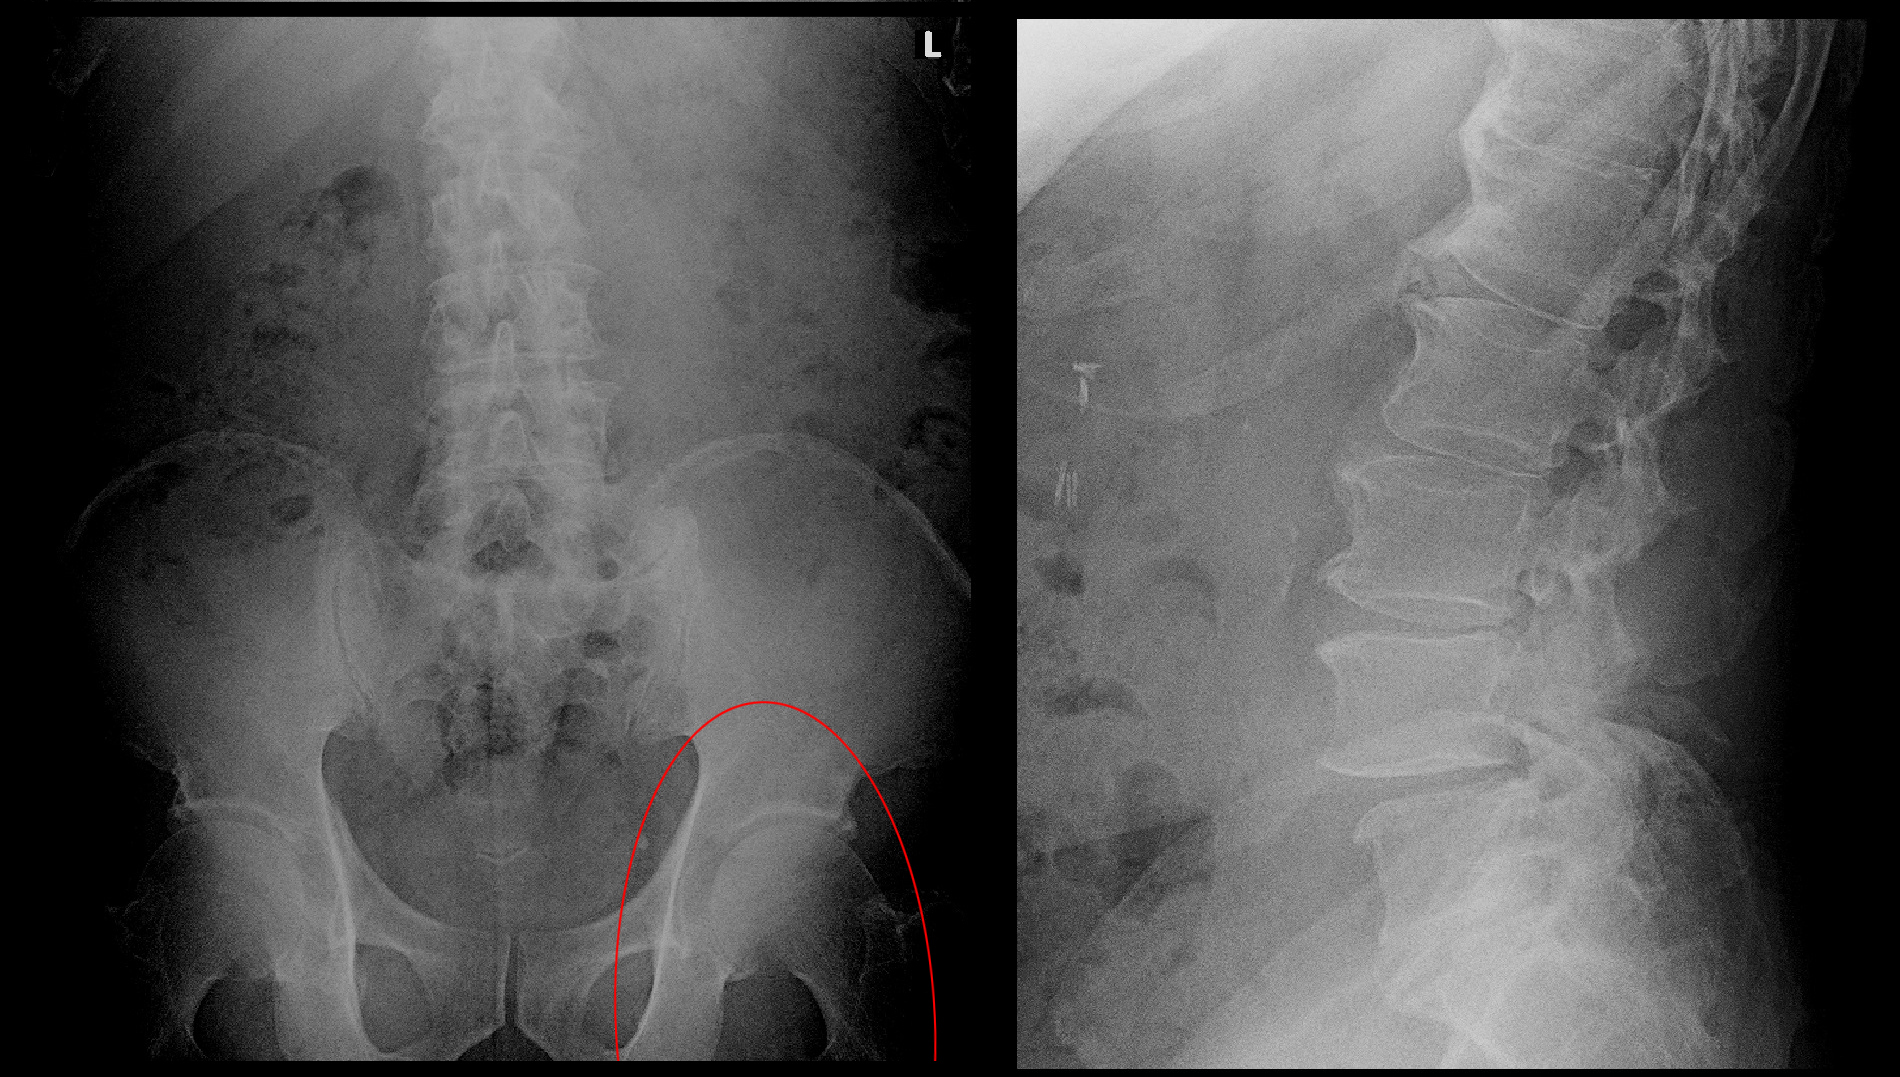

75才の男性です。

令和7年9月27日朝突然に左臀部痛が発症しました。徐々に左下肢全体の痛み(医師は坐骨神経痛と表現します)となり、即日当院を受診されました。立っていることも座っていることもできず、左下で横になっていると楽ということで待合でも左側臥位をとっていました。この患者さんは令和2年4月30日も右腰痛で当院を受診していてMRI検査を受けていました。この時は服薬のみで症状の軽減がえられていました。